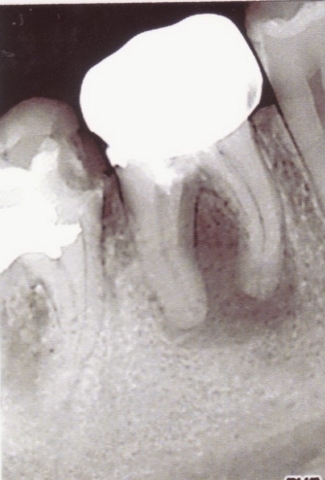

В поликлинике внедрены современные методы лечения и протезирования зубов, включая протезирование с использованием имплантатов, депофорез гидроокиси меди-кальция при лечении радикулярных кист челюстей, исправление прикуса с использованием брекет-систем.

Примеры лечения радикулярных кист челюстей без скальпеля:

Фото: до лечения депофорезом

Фото: после лечения депофорезом